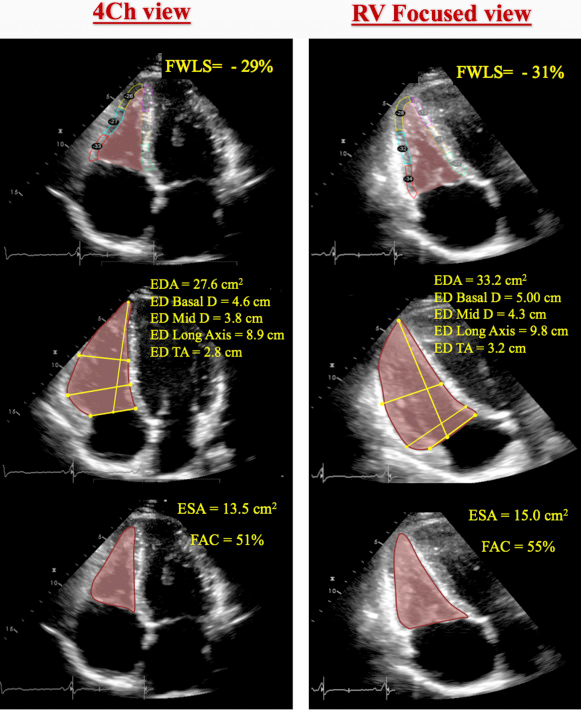

The conventional apical four-chamber view (i.e., focused on the left ventricle) results in considerable variability in how the right heart is sectioned, and consequently, RV linear dimensions and areas may vary widely in the same patient with relatively minor rotations in transducer position (Figure 7B). RV dimensions are best estimated from a RV-focused apical four-chamber view obtained with either lateral or medial transducer orientation (Figure 7A and Table 7). Care should be taken to obtain the image with the LV apex at the center of the scanning sector, while displaying the largest basal RV diameter and thus avoiding foreshortening. Of note, the accuracy of RV measurements may be limited when the RV free wall is not well defined because of the dimension of the ventricle itself or its position behind the sternum. Recent data have suggested that indexing RV “size” to BSA may be relevant in some circumstances, but the measurements used in those studies lacked the reference points of the RV-focused view and frequently used RV areas, rather than linear dimensions. 2

- 🌟RV focused A4C View: LV apex is at the top of the view, but angulated transducer to tip the RV into better view. This view allows you to measure the maximal RV diameter.

- This is the view that you will want to use to take measurements for RV size

Fractional Area Change (Poor Man’s EF)

- Obtain in RV focused A4C view

- Values < 35% are consistent with RV dysfunction

Longitudinal strain is calculated as the percentage of systolic shortening of the RV free wall from base to apex, while longitudinal strain rate is the rate of this shortening. 2

- Should be measured in the RV-focused A4C view